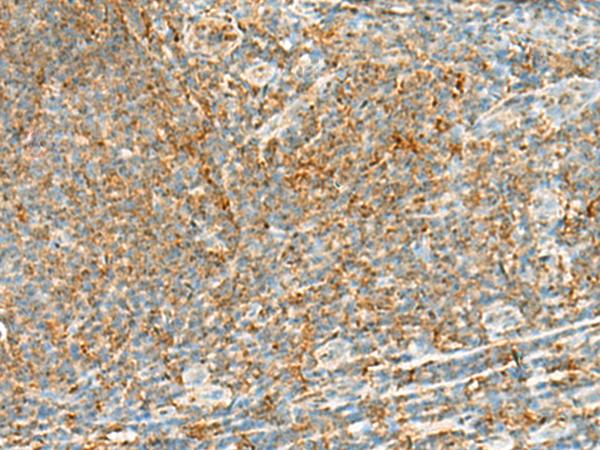

IHC positive control: |

Human tonsil |